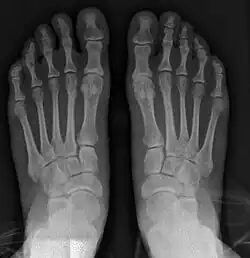

Fig. 8a. Painful hallux valgus and metatarsus primus varus deformity recurrence of left foot after osteotomy surgery